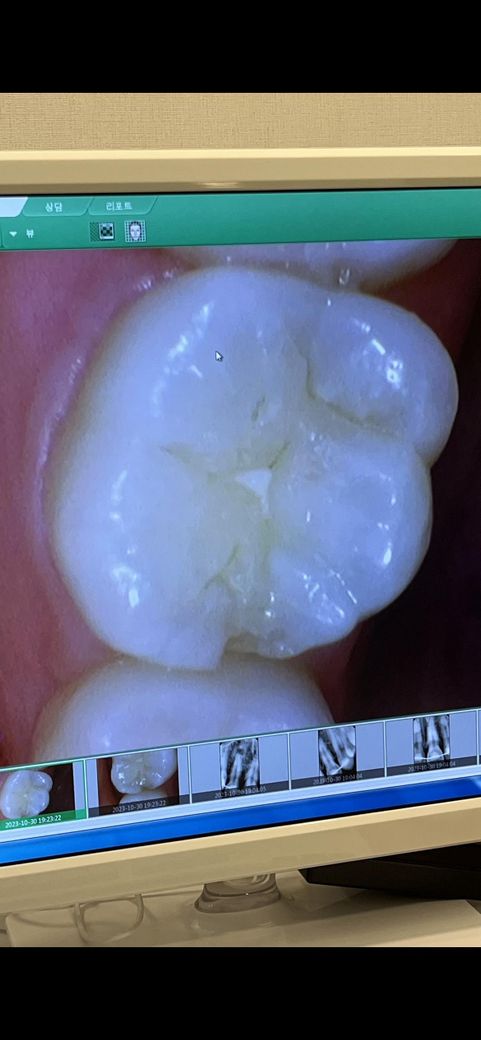

모서리가 깨져서 인레이를 해야한다는 소견을 들었는데요…

인레이를 하려면 치아 삭제량이 생기다보니 그게 너무 아깝게 느껴져요

이정도 깨짐이면 무조건 인레이 치료 해야하나요??

살짝 다듬거나 레진으로 떼우는 방법으로는 치료 불가능한지 궁급합니다!

현재 사진상의 깨짐이면 인레이 치료가 필요로 되며, 레진충진시에는 모서리부위이기에 다시 떨어져나갈 우려가 있습니다.

깨진 범위가 넓지 않기 때문에 인레이 치료를 할 수도 있지만 레진으로도 간단하게 충전이 가능할 것으로 생각 됩니다.

치아 사이가 깨진경우에는 인레이를 많이 합니다. 다른곳에 치료한것도 떨어져 나간거 같으니 인레이를 하시면될것같습니다.

안타깝게도 옆면이 깨졌기 때문에 레진으로 해둔다면 인접한 옆 치아와의 접촉면이 덜 정교할 수 있어 이차충치가 생길 우려가 높긴 합니다. 물론 레진으로 잘 하는 경우도 있지만 인레이가 더 깔끔하고 정교하게 치료되는 방향이긴 합니다. 일반적으론 그렇고 레진을 더 선호하는 치과의사도 있으니 다양한 치과에 전화로 문의해보시는 것도 좋을 것 같습니다

더불어 씹는면에도 충치가 조금 진행되었습니다